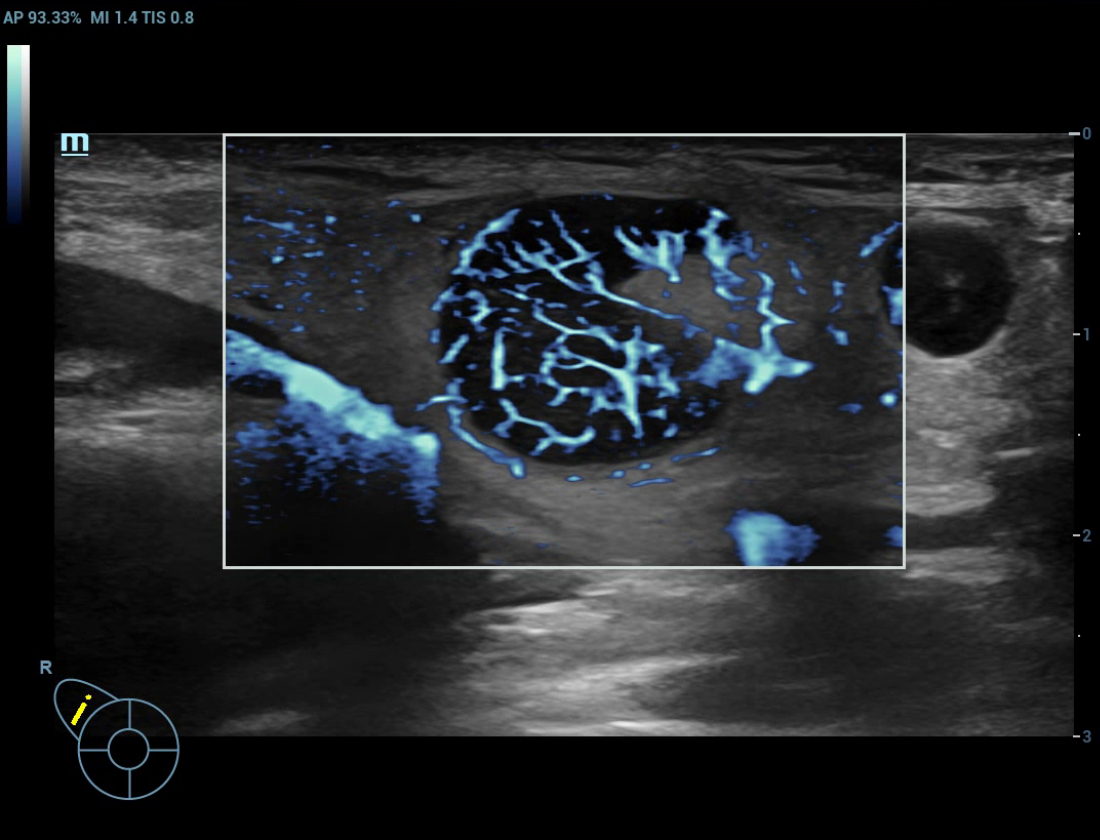

Ultra-Micro-angiografie (UMA)

UMA verbetert het diagnostische vertrouwen door de zichtbaarheid van de bloedstromen uit te breiden tot op het kleinste vaatniveau, met een superieure gevoeligheid en resolutie van de bloedstroom.

sUMA Schildklierkanker

Beeldengalerij

Borstmassa cUMA

Borstmassa